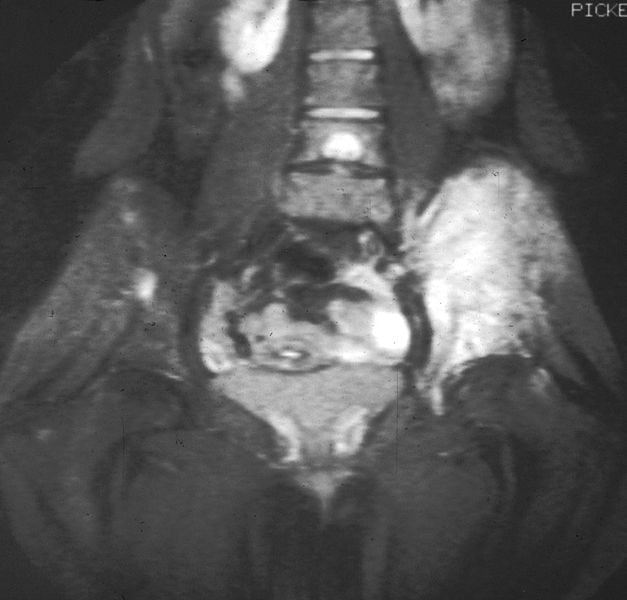

El sarcoma de Ewing es un tipo de cáncer bastante raro y agresivo, el cual se presenta en los huesos o en el tejido blando alrededor de los mismos.

Por lo general se localiza en los huesos de las piernas y la pelvis, siendo contados los casos donde se manifiesta en zonas del pecho, abdomen o extremidades superiores.